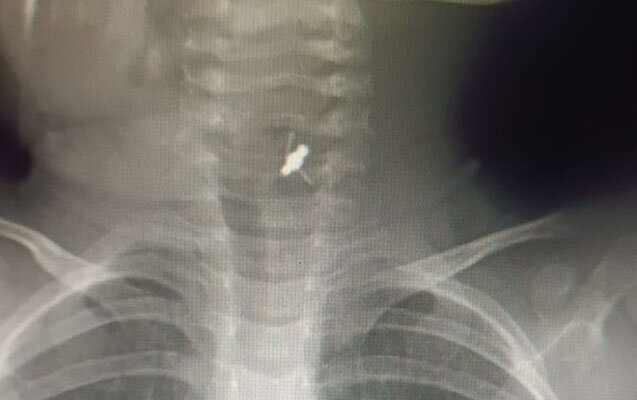

2 yaşlı uşaq saç sancağı uddu - Foto

Saç sancağı udan 2 yaşlı uşaq xilas edilib.

Həkim qeyd edib ki, azyaşlı tibb müəssisəsinə tənəffüs çatışmazlığı və boğulma şikayətləri ilə gətirilib:

"Aparılan müayinələr əsasında xəstənin yad cisim udduğu məlum olub. Xəstəyə bronxoskopiya icra edilərək baş bronx mənfəzindən yad cisim-saç sancağı xaric edilib".